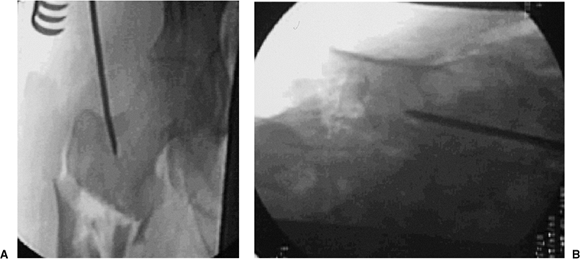

![]() |

Figure 20.5. Skin incision.

Figure 20.6. A,B. Tip-threaded guide pin inserted into piriformis fossa, centered on lateral view.

crucial. Incorrect starting points can lead to angular deformities. For

conventional, reamed, piriformis, intramedullary nailing, the correct

starting point is in the piriformis fossa. However, for reconstruction

nailing, the portal of entry is slightly anterior to the fossa. Because

the femoral neck arises from the anterior portion of the proximal

femur, moving the starting point 3 to 4 mm anteriorly facilitates

proximal screw insertion. A 3.2-mm threaded guide pin is inserted at

the entry site and confirmed by fluoroscopy to be in the midline of the

femur in both AP and lateral views (Fig. 20.6). The entry portal is enlarged with the cannulated reamer over the guide pin (Fig. 20.7).